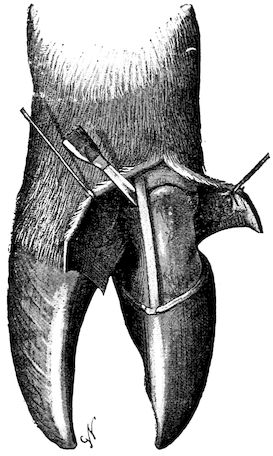

Fig. 8.—Transverse section through the middle region of the face in a pig suffering from osseous cachexia.

18In the final stages, the bones may be cut with a knife, and a time arrives when bony tissue seems completely to have disappeared; thus, as shown in Fig. 8 herewith, it was possible to cut the entire head of a pig into thin slices without the slightest difficulty. All parts of the head had been affected by the softening change.

From the chemical point of view, the diminution in mineral salts and in phosphate of calcium has long been recognised, but the degree of this change varies according to the phase. In human beings the proportions have been estimated as follows: Normal bone, 50 to 80 per cent. of phosphate of calcium; bone in persons suffering from osteomalacia, 5 to 20 per cent. of phosphate of calcium. The changes in the ossein have not been carefully studied. We only know that histologically the ossein becomes fibrillar, and that chemically it no longer retains its normal composition.